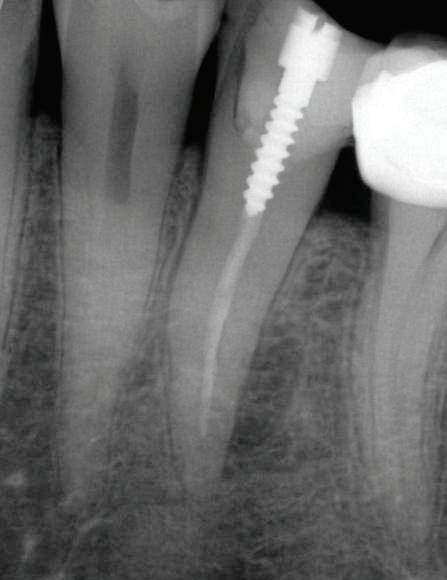

Abb. 3: Präoperatives Röntgenbild Zahn 35,

endodontische Obturation und ein Metallstift sind sichtbar. Radiotransparente Läsion als periapikale Parodontitis ist seitlich an der distalen Seite der Wurzel zu erkennen. – Abb. 4: Postoperatives Röntgenbild Zahn 35 (mit noch auf Zahn befindlichem Kofferdam). Vollständige und kompakte Füllung des endodontischen Raums mit der Füllung eines seitlichen Kanals und einer kleinen Extrusion von Sealer durch diesen hindurch an der Stelle der seitlichen radiotransparenten Läsion. – Abb. 5: Kontrollaufnahme nach zwölf Monaten. Abheilung der lateralen radiotransparenten Läsion.

Das postoperative periapikale Röntgenbild zeigte eine optimale Adaption des verwendeten Obturationsmaterials sowie die Füllung eines großen distalen Lateralkanals, der wahrscheinlich die Ursache für die periapikale Läsion und damit die beschriebene Symptomatik war (Abb. 4). Die Röntgenuntersuchung nach einem Jahr bestätigte die abgeheilte periapikale Läsion. Die Patientin berichtete, dass sie in jener Zeit keinerlei Symptome mehr zu beklagen hatte (Abb. 5).